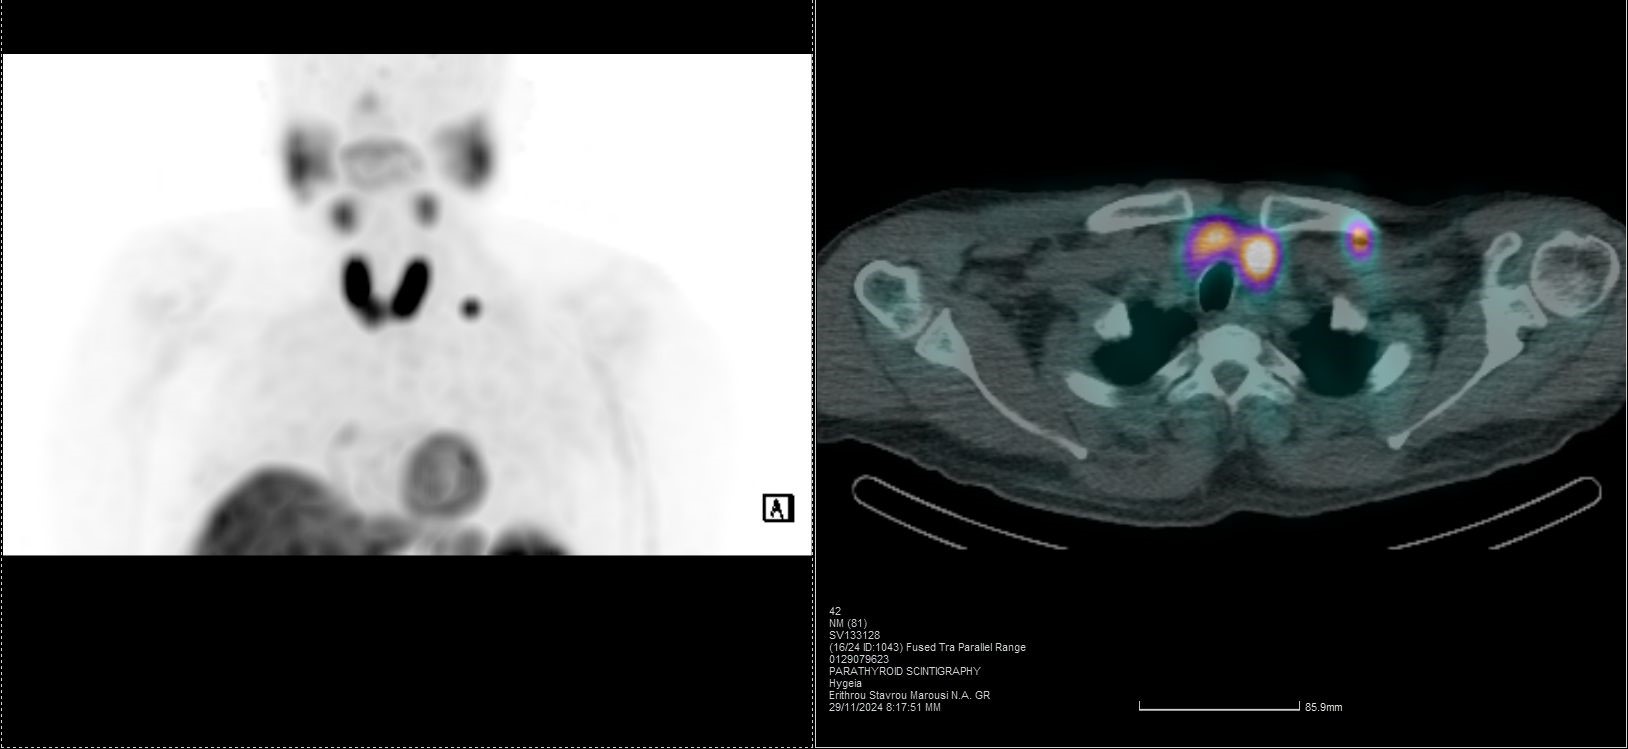

Οι περισσότερες διαγνωστικές εξετάσεις της Πυρηνικής Ιατρικής είναι γνωστές ως σπινθηρογραφήματα, τα οποία στη σύγχρονη εποχή πραγματοποιούνται με τη βοήθεια της γ-κάμερας (γ-camera) ή συστημάτων SPECT/CT, που επιτρέπουν απεικόνιση υψηλής ακρίβειας και λειτουργική ανάλυση σε μοριακό επίπεδο.

Tο Νοσοκομείο ΥΓΕΙΑ είναι το μοναδικό με πάνω από 15 χρόνια εμπειρία στην SPECT CT Aπεικόνιση. Από το 2024 διαθέτει δύο υπερσύγχρονες τομογραφικές γ-κάμερες της Siemens – Symbia Pro.specta SPECT/CT with myExam Companion. Πρόκειται για συστήματα τελευταίας γενιάς που συνδυάζουν υψηλή απεικονιστική ακρίβεια, χαμηλή δόση ακτινοβολίας και πλήρη αυτοματοποίηση της διαδικασίας. Με την χρήση ειδικού σύγχρονου λογισμικού (SIEMENS SYNGO) εξασφαλίζεται η μέγιστη ποιότητα εικόνας. Ειδικότερα οι γ-κάμερες χαρακτηρίζονται από τα εξής: